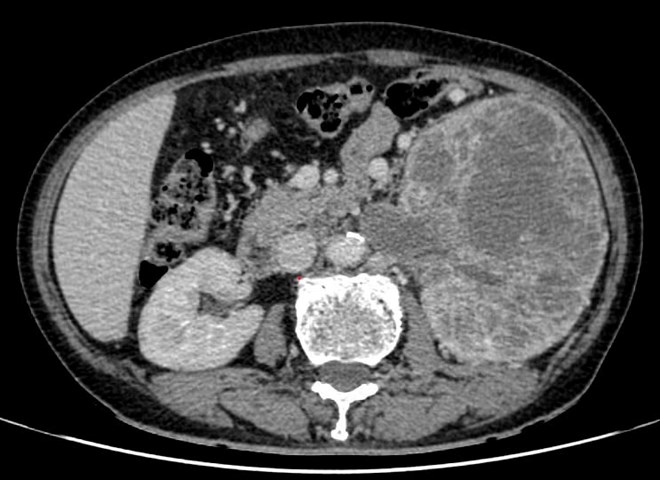

Hình ảnh chụp CT khối u ở thận xâm lấn tĩnh mạch chủ dưới. Ảnh: BVCC

Trước đó, bệnh nhân khỏe mạnh, chưa từng phát hiện bệnh lý. Kết quả thăm khám và chẩn đoán hình ảnh cho thấy khối u ở thận trái kích thước khoảng 15 x 20 cm, phá hủy hoàn toàn cấu trúc nhu mô thận, xâm lấn đài – bể thận.

Đáng chú ý, khối u đã gây huyết khối trong tĩnh mạch thận, lan tới tĩnh mạch chủ dưới, làm tăng nguy cơ tắc mạch hoặc thuyên tắc mạch phổi đe dọa tính mạng.